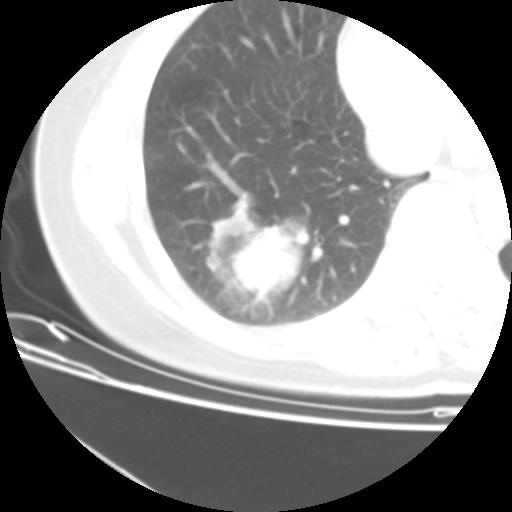

右肺下叶类癌

女 46岁,咳嗽咳血10月

【linyiming】右肺下叶见类圆形软组织影,边缘欠规整,略分叶状。考虑炎症假瘤可能?

未排除周围型肺癌。建议CT增强。

【刚起步】只有想不到的,没有长不到的。实性结节,强化明显,病人咳血,肺癌不能除外。

【aosangwa】肺癌的主要特征是:毛刺征、分叶征及胸膜凹陷征,此病例位于右肺下叶距胸膜很近,但没有胸膜凹陷征,其周围像示渗出性病变,病灶在两窗上没有大小没有发生大小改变。

考虑其良性肿瘤,炎性假瘤可能性大,其主要鉴别是:结核球、周围型肺癌、血管瘤

病理诊断类癌(周围型)。